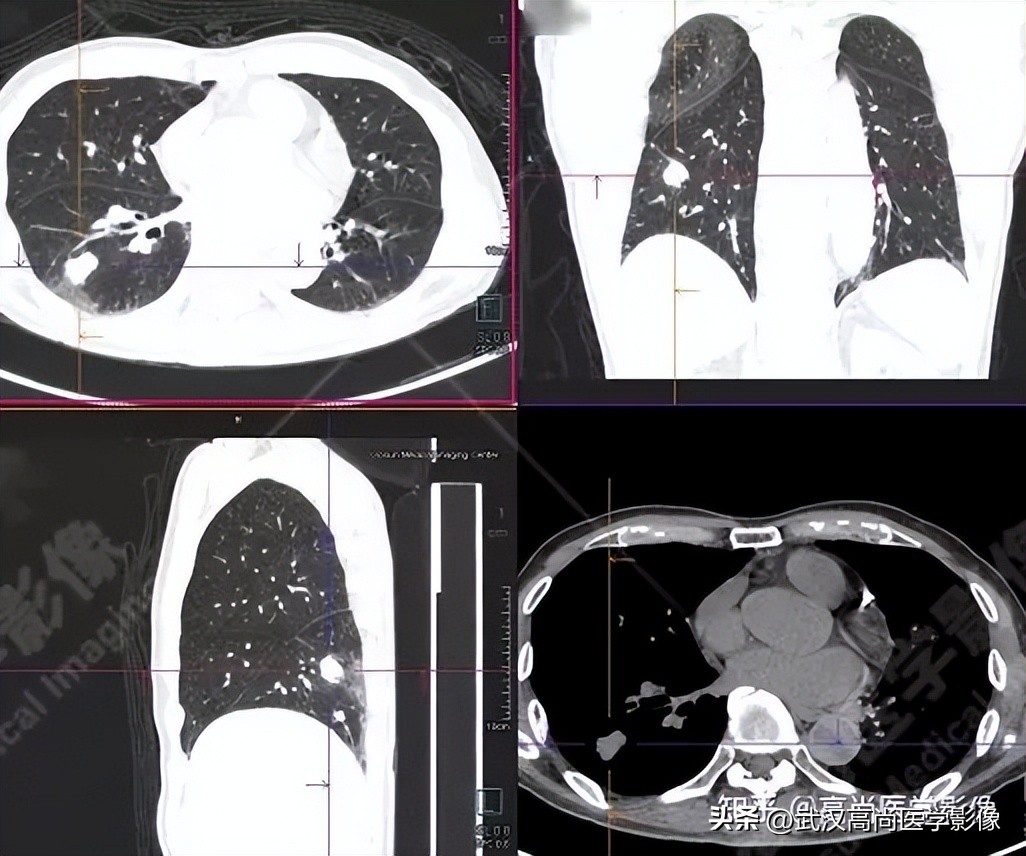

病例三

老年男性63岁,左大腿疼痛1月余,渐加重。

MR检查提示左股骨上段破坏,需排查转移。

左股骨上段溶骨性骨质破坏,SUVmax4.7,怀疑为转移。

全身PET/CT

影像表现:

右肺上叶尖段胸膜下见一实性结节,范围约1.6cm×1.3cm,病灶紧贴邻近胸膜,伴牵拉增厚,FDG高摄取,SUVmax为7.5。

恶性CT征象:

结节边缘不光整,分叶、长短不一的毛刺,邻近胸膜牵拉明显。

右侧胸膜区多发条片状代谢增高影,SUVmax4.7,CT于相应部位胸膜增厚,伴右侧中量胸水。

PET代谢增高,在发现胸膜转移较常规CT扫描有一定的优势。

PET/CT诊断结论

右肺上叶尖段周围型肺癌,累及邻近胸膜;右侧胸膜多发转移,伴中等量胸水;左股骨上段转移。

另外,左肺上叶前段见一团状混杂磨玻璃影,范围约4.3cm×3.3cm,CT值约-662Hu,内部扭曲扩张支气管及血管影穿行,边缘分叶、棘状突起,FDG摄取轻度增高,SUVmax1.3,考虑为多中心起源浸润性肺癌(多原发的肺癌)。